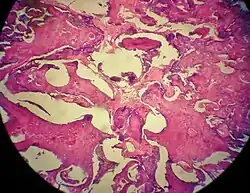

Histopathology

Odontomas are from mixed epithelial and mesenchymal components which are required for tooth development, producing enamel, dentine, cementum and pulp tissue.[6]